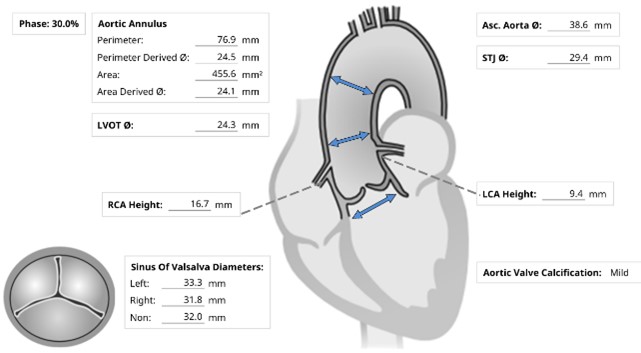

Initial ECG revealed AF. Transthoracic echocardiography revealed concentric LVH with a 70 % of left ventricular systolic function, normal right ventricular systolic function, bi-atrial enlargement and severe calcific aortic stenosis which classified as stage D1 (AVA 0.98 cm2 by AV VTI, AV Vmax 4.03 m/s, mean AV pressure gradient 38.21 mmHg). Following as the Heart Team discussion, Transcatheter Aortic Replacement (TAVR) following coronary angiography (CAG) was scheduled as the optimal choice.

Under local anesthesia and conscious sedation, femoral arteries (FA) were accessed by 8-Fr sheath at right FA and two of 8-Fr sheaths at left FA for pigtail catheter and snare-assisted device. Aortography was conducted by pigtail catheter to locate aortic cusp. An Amplatz left catheter over a 0.035-inchJ-tip wire was placed at aortic cusp via the RFA which was then exchanged with an Amplatz Super Stiff wire to upsized 16-Fr Braidin sheath. The aortic valve was crossed with an Amplatz left catheter over a straight-tip wire under cuspoverlap views (LAO16, CAU 30), peak-to-peak gradient of 19 mmHg. During RV pacing, a Safari Extra Small guidewirewas positioned in LV and the AV was pre-dilated by an 18 × 40 mm Alwide balloon. Subsequently, a 27 mm VitaFlow valve was deployed in an optimal position under snare-assisted. Post-deployment aortography revealed mild AR, LVEDP of20 mmHg, and 4 mmHg of LVOT gradient. Post-dilation was performed by a 24 × 40mm VACC III balloon. The FA was closed by 6-Fr Proglide at the right and 8-Fr AngioSeal at the left. Post-TAVR TEE showed mild PVL without significant transvalvular gradient and preserved LVEF of 64%. One-month after the TAVR, she was diagnosed with early-stage colonic cancer. A laparoscopic hemicolectomy which completed pre-operative evaluation, coronary revascularization, TAVR and appropriated medication was performed as time-sensitive surgery following by CMT with curative intent.